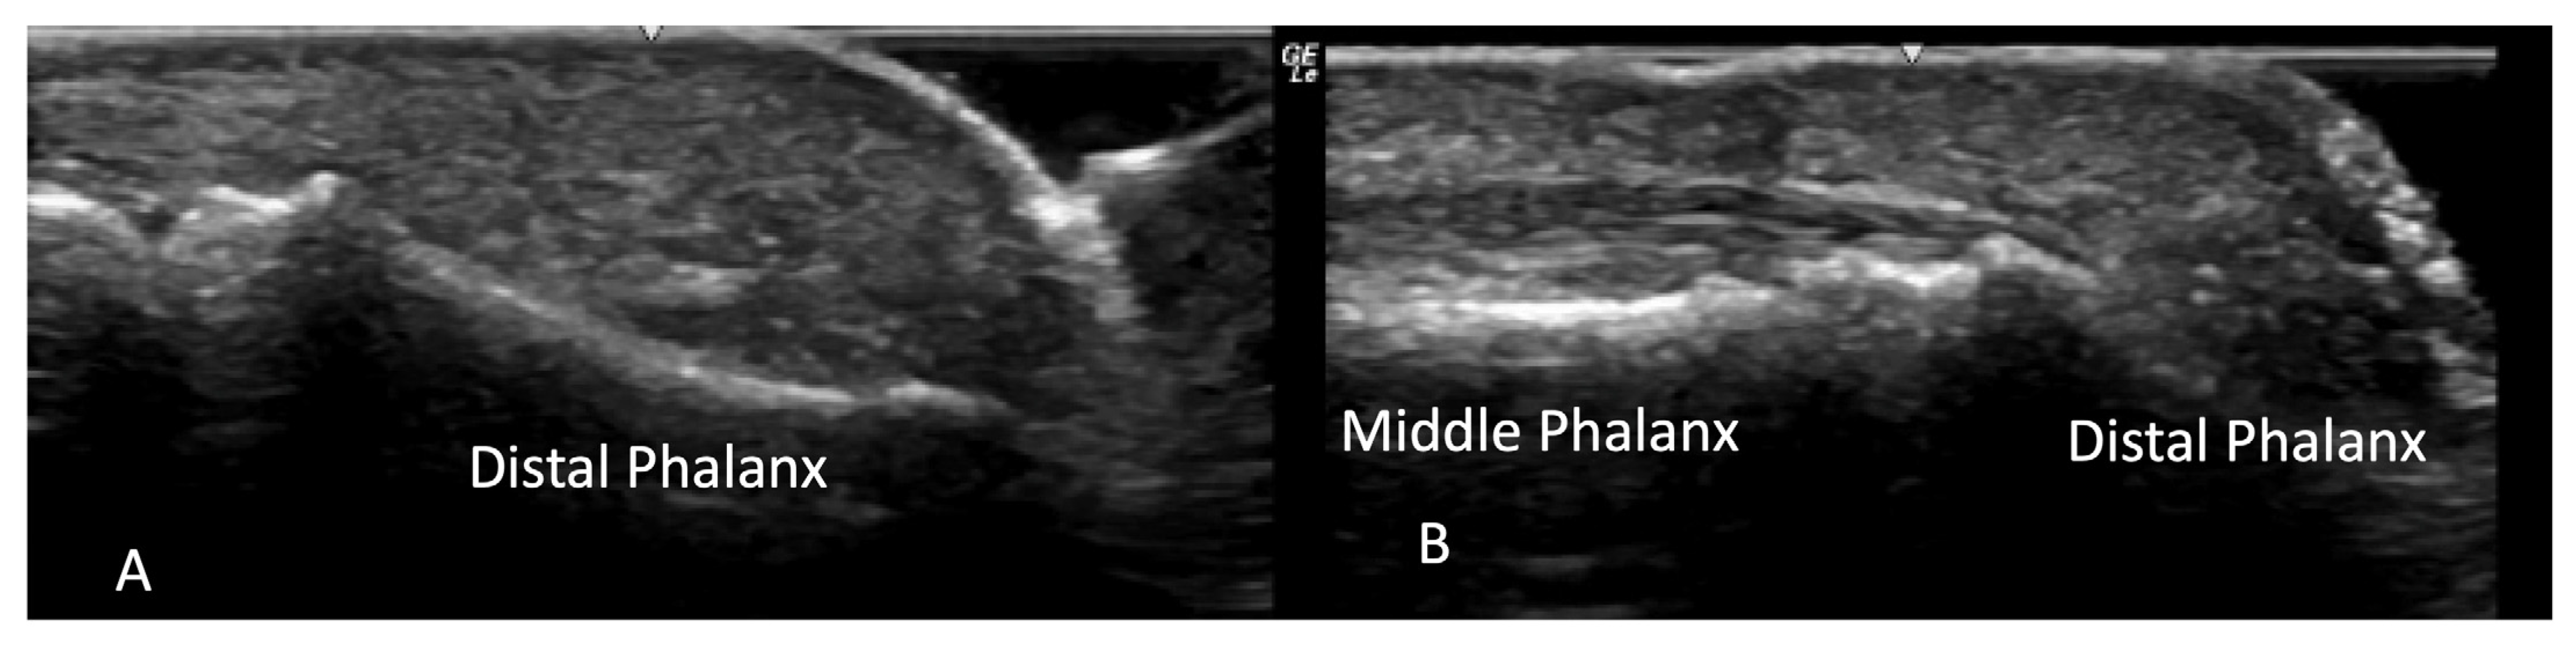

2.1.3. Acro-Osteolysis

2.2. Tendon Pathology

2.2.2. Contractures and Tendon Friction Rubs